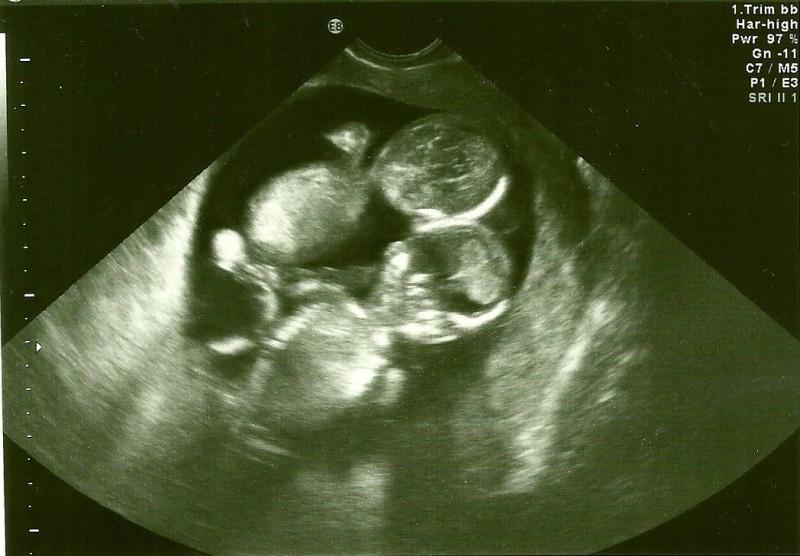

A mers la spital pentru prima ei ecografie. Când medicul a văzut imaginea a înghețat, a trimis-o acasă și i-a spus să se roage la Cel de Sus. Ce s-a întâmplat la naștere